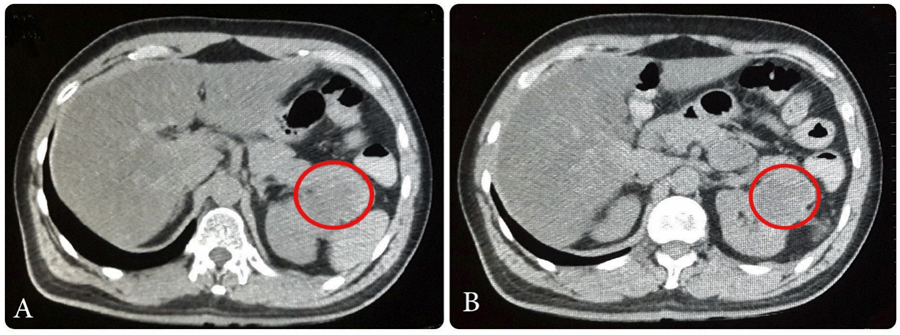

A 50-year-old male presented with history of hypertension and hemorrhagic stroke in 2012 with sequel of right hemiparesis. The patient presented with a right supraclavicular firm, incompressible and immobile swelling of 55 mm. Body computed tomography (CT) with contrast was done. It showed left renal mass in lower pole measuring 65x38 mm as a focal bulging of the renal contour, mainly isodense to the renal parenchyma. The corticomedullary phase clearly showed renal malignancy which was moderately and heterogeneously enhancing (Figure 1). Heterogeneous contrast enhancement on imaging should always suggest renal malignancy preoperatively. There was a secondary heterogeneous lesion in the right supraclavicular hollow measuring 56x42 mm with central necrosis (Figure 2). Fine needle aspiration (FNA) of right supraclavicular tumor showed metastasis of well differentiated adenocarcinoma. His biopsy was unsatisfactory. He was evaluated by urology and oncology services so it was decided to like radiotherapy for local control and subsequen treatment with interferon α 5 million IU/week and sunitinib 50 mg/day for one year for down staging (six weeks cycles). Treatment was started with pazopanib 800 mg/day. The lesion increased in size for six months. He had poor clinical response. He was evaluated by head and neck surgeons and surgery was done: resection of cervical tumor of level V and right cervical lymphadenectomy of levels II, III, IV, V (Figure 3). The surgery was done on third day of hospitalization. Ambulatory monitoring was done by head and neck and oncology services. Microscopic study of respected lymph nodes revealed clear cell renal carcinoma (ccRc). After 45 days, laparoscopic nephrectomy was performed. The immunohistochemical profile was the same for both the neck and renal tumor. No recurrences occurred after two years of follow-up.

Figure 1: TC: Left renal primary typical tumor. A) Lower pole left renal mass of 65x38 mm as a focal bulging of the renal contour mainly isodense to the renal parenchyma; B) The corticomedullary phase clearly shows renal malignancy moderately and heterogeneously enhancing.